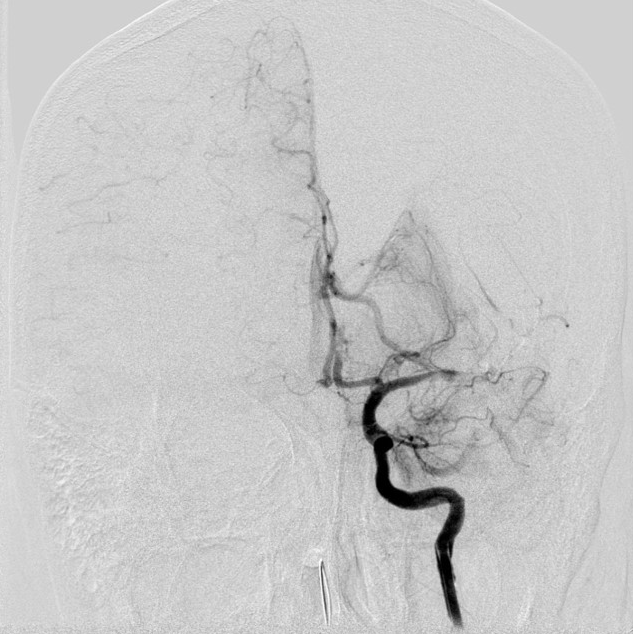

单弯导管辅助长泥鳅导丝置于LC1末端,交换Infinity长鞘至LC1,DSA:LM闭塞。

动脉长鞘怎么置入【沙场点兵 有史可鉴】Trevo ProVue联合Infinity长鞘经桡动脉取栓分享_https://www.jmylbn.com_新闻资讯_第11张

动脉长鞘怎么置入【沙场点兵 有史可鉴】Trevo ProVue联合Infinity长鞘经桡动脉取栓分享_https://www.jmylbn.com_新闻资讯_第12张

动脉长鞘怎么置入【沙场点兵 有史可鉴】Trevo ProVue联合Infinity长鞘经桡动脉取栓分享_https://www.jmylbn.com_新闻资讯_第13张